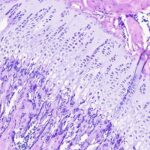

La trombocitopenia en el contexto de neoplasias hematológicas constituye una alteración hematológica compleja en la que confluyen mecanismos fisiopatológicos múltiples, con implicaciones clínicas que trascienden la simple disminución cuantitativa de…